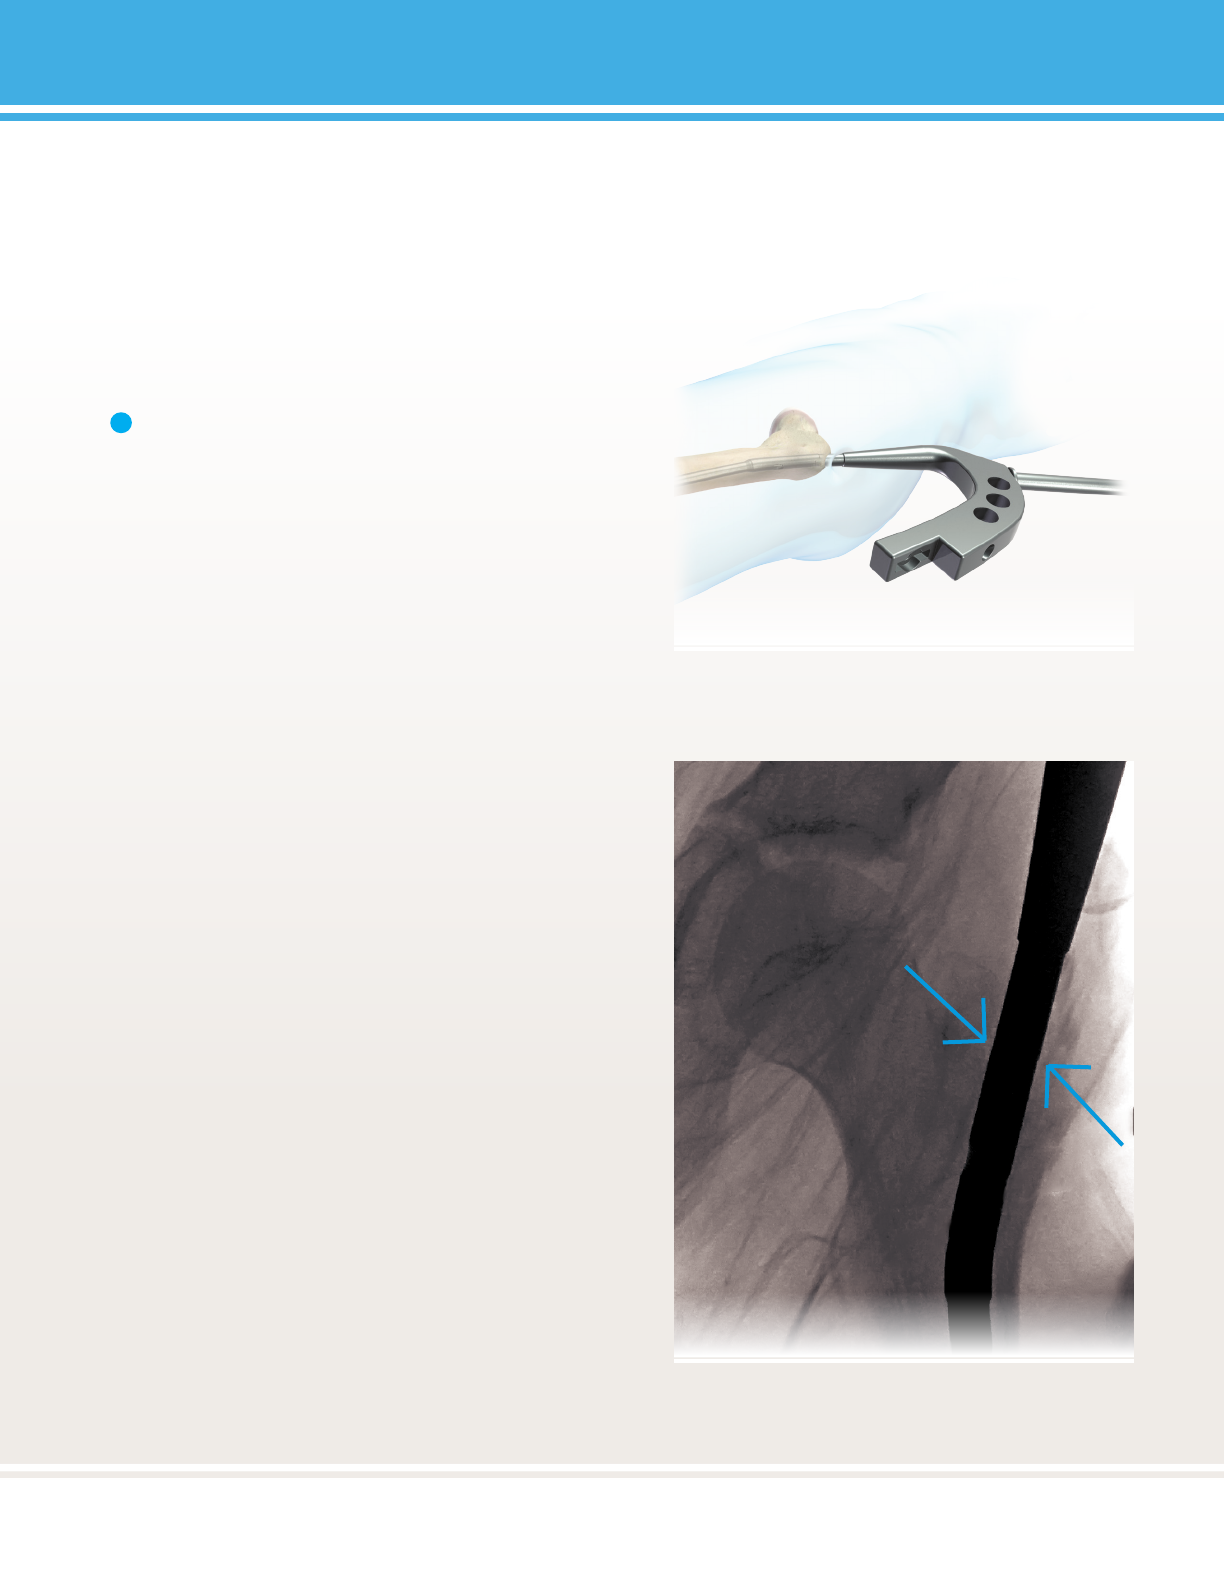

FIGURE 30:

FIGURE 31:

Note: Do not apply excessive force to the targeng

construct or targeng might be compromised.